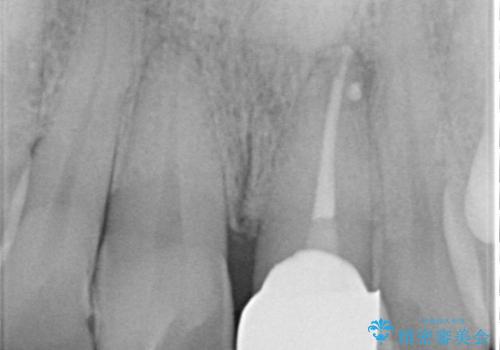

- かけてしまった前歯をきれいにしたいとのことで来院されました。

レントゲンを撮影すると、根の神経の治療が必要なことがわかりました。

根管治療を行いセラミックを装着する計画としました。